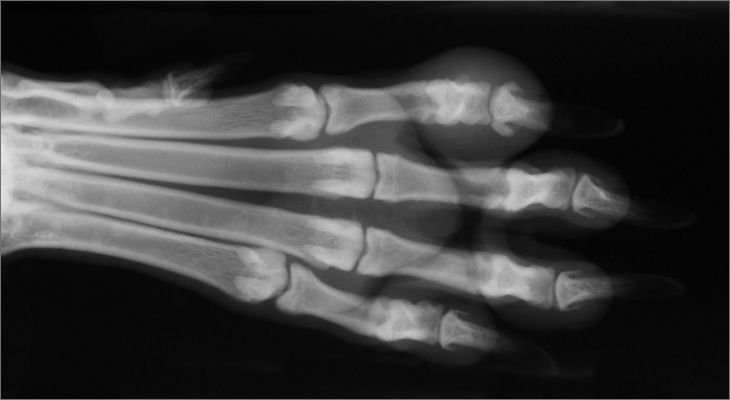

When health problems develop, practitioners must diagnose the problem and treat the patients. Accurate diagnosis frequently requires the use of laboratory tests, radiography or x-rays, and specialized equipment. Treatments may involve a number of procedures including emergency lifesaving measures, prescribing medication, setting a fracture, delivering a calf, performing surgery, or advising the owner on feeding and care of the patient.